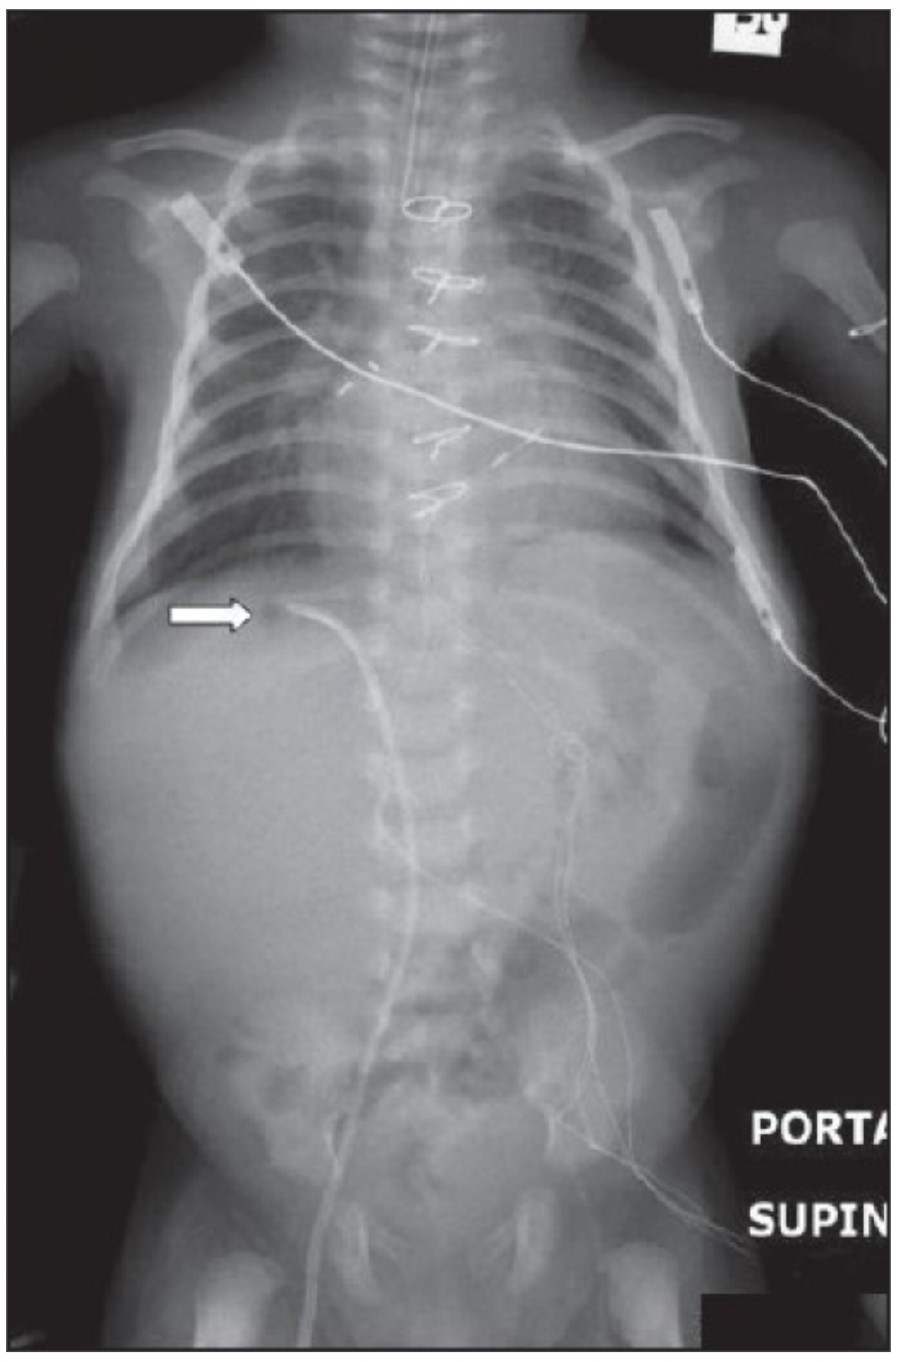

중환자에서 pneumothorax의 진단은 종종 supine radiograph에서 내릴 수 있다. Supine position에서 공기는 anteromedial 방향으로 모이게 되는데, apical air collection이 있을 경우 large pneumothorax가 있음을 시사한다. 공기는 lung과 diaphragm 사이의 subpulmonic location에 trap 되어 있을 수도 있다. 공기가 costophrenic sulcus로 anterolateral extension 될 경우, 이 costophrenic sulcus의 radiolucency를 증가시키는데, 이를 deep sulcus sign이라고 한다. Subpulmonic pneumothorax의 다른 특징으로 diaphragm의 superior surface와 IVC 윗부분이 뚜렷하게 보일 수 있다.

중환자에서 tension pneumothorax의 진단은 매우 힘들다. ARDS와 같은 lung의 병리적인 기전이 lung compliance를 감소시킴으로써 total lumg collapse를 막는다. 또한 tension pneumothorax의 특징인 mediastinal shift가 PEEP으로 인해 나타나지 않을 수 있다. Chest X ray 상에서 tension pneumothorax는 hemidiaphragm의 depression이나 heart border, SVC, IVC의 이동으로 나타날 수 있다.